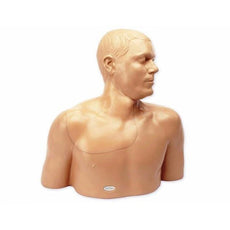

Gen II Ultrasound Central Line Model with Transparent Insert

Each model offers anatomically correct vascular anatomy of the right upper thorax and neck including the internal

jugular vein, brachiocephalic vein, subclavian vein, axillary vein, carotid artery, subclavian artery, and axillary

artery, as well as anatomical landmarks including the clavicle, the two heads of the sternocleidomastoid muscle, and the

sternal notch. Users can utilize traditional anatomical landmarks for blind insertion techniques, or utilize ultrasound

to obtain images of anatomical structures. A simulated SVC accommodates full threading of guidewires, dilators and

central line catheter placement. Venous and arterial fluids that are removed during central catheter insertions training

are easily refilled using quick fill ports. Users can run intravenous fluid for constant refill of vessels during

training.

Gen II Ultrasound Central Line Model with Transparent Insert

Gen II Ultrasound Central Line Model with Transparent Insert and Hand Pump | CAE Blue Phantom

Brand New! 2nd Generation upper torso ultrasound guided central line placement training model with transparent tissue insert allows users to develop and practice the skills necessary to gain proficiency in using ultrasound to guide central catheter insertions in the internal jugular vein (IJ), subclavian vein, and axillary vein while revealing the venous and arterial vessels as well as accessory boney structures. Developed with the goal of helping clinicians bridge the learning gap by allowing them to see the internal anatomical structures with their eyes as well as with ultrasound imaging, our transparent central line placement tissue offers superb ultrasound hands-on training. Using Blue Phantom proprietary simulated human tissue, this very realistic and ultra-durable transparent central venous access ultrasound training model is excellent for training clinicians in the psychomotor skills associated with ultrasound guided central line placement procedures. These ultrasound imaging skills include; using ultrasound system controls, transducer positioning and movement, recognition of arterial and venous anatomy, using ultrasound to target the appropriate vessels for cannulation, and performing a central venous access procedure.Helps

clinicians bridge the learning gap by allowing them to see the internal anatomical structures with their eyes as

well as with ultrasound imaging.

- Contains anatomically correct vascular anatomy of the right upper thorax and neck including the internal jugular vein, brachiocephalic vein, subclavian vein, axillary vein, carotid artery, subclavian artery, and axillary artery, as well as anatomical landmarks including the clavicle, the two heads of the sternocleidomastoid muscle, and the sternal notch

Gen II Ultrasound Central Line Model with Transparent Insert

- Contains anatomically correct vascular anatomy of the right upper thorax and neck including the internal jugular vein, brachiocephalic vein, subclavian vein, axillary vein, carotid artery, subclavian artery, and axillary artery, as well as anatomical landmarks including the clavicle, the two heads of the sternocleidomastoid muscle, and the sternal notch

- Size 17” x 11” x 17” (43cm x 28cm x 43cm) (L x W x H)

- Weight 20 lbs. (9 Kg.)